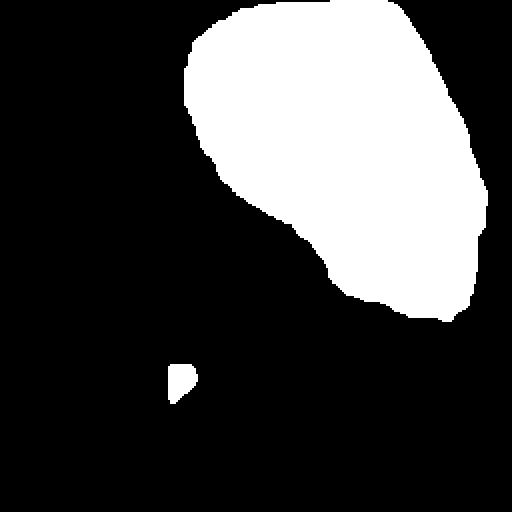

A few sample images and the corresponding masks of the polyp dataset in HyperKvasir are shown in Fig 2. The polyp images are RGB images. The masks of the polyp images are single-channel images with white () for true pixels, which represent polyp regions, and black () for false pixels, which represent clean colon or background regions. In this dataset, there are different sizes of polyps. The distribution of polyp sizes as a percentage of the full image size is presented in the histogram plot in Fig 3, and we can observe that there are more relatively small polyps compared to larger polyps. Additionally, a subset of this dataset was used to prove that the performance of segmentation models trained with small datasets can be improved using our SinGAN-Seg pipeline, and the whole dataset was used to show the effect of using SinGAN-Seg generated synthetic images instead of a large dataset which has enough data to train segmentation models. In this regard, this dataset was used for two purposes:

After training SinGAN-Seg models, we generated random samples per real image using the input scale , which is the lowest scale that uses a random noise input instead of a re-scaled input image. For more details about these scaling numbers and corresponding output behaviors, please refer to the vanilla SinGAN paper [56]. Three randomly selected training images and the corresponding first synthetic images generated using scale are depicted in Fig 4. The first column of the figure represents the real images and the ground truth mask annotated from experts. The rest of the columns represent randomly generated synthetic images and the corresponding generated mask.